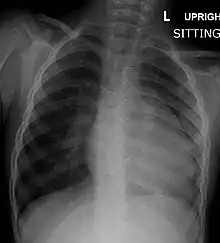

A chest X-ray of a child with tetralogy of Fallot

Before more sophisticated techniques became available, chest X-ray was the definitive method of diagnosis. The abnormal "coeur-en-sabot" (boot-like) appearance of a heart with tetralogy of Fallot is classically visible via chest X-ray, although most infants with tetralogy may not show this finding.[49] The boot like shape is due to the right ventricular hypertrophy present in TOF. Lung fields are often dark (absence of interstitial lung markings) due to decreased pulmonary blood flow.[50]:171–72